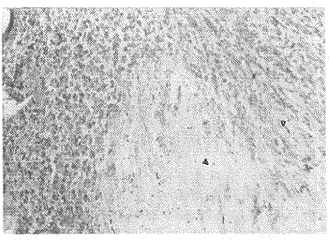

图2 缺血心肌组织呈浅棕色,孤立状(△),正常心肌不着色(▲);d, 百拇医药

Fig2 Ischemic myocardia tissus stained light-brown,iso-leted gramele(△),normal yocardium did not be staind (▲)(ABC×120)

2.2 抗cTnT对缺血和坏死心肌定位观察 正常心肌不着色,缺血心肌着色较浅,呈散在孤立状。坏死心肌主要为不均一性、聚集成团,棕褐色着色(见图1~图3)。同一组织作HE染色对照可见坏死区心肌细胞核部分溶解消失,部分破裂成碎片或固缩状。细胞结构明显破坏,大量炎性细胞浸润(见图4)。